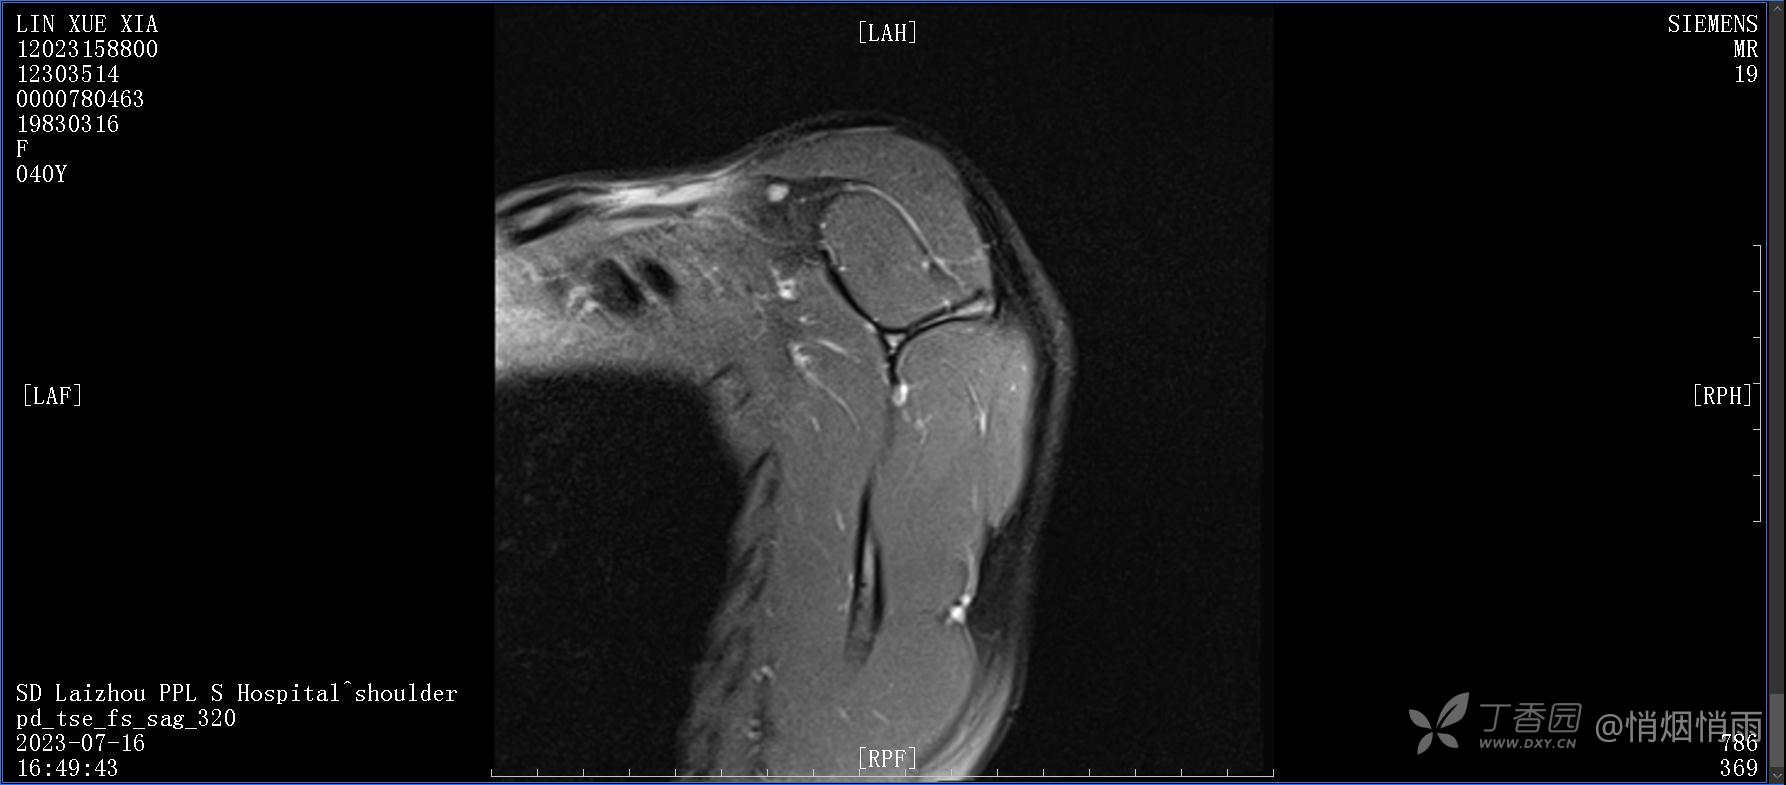

查体:右肩关节局部轻度肿胀,肩胛区压痛明显,痛处不固定,肩关节痛性活动受限,jobe test(+),lift -off test(+),中指、环指感觉较余指减退,余肢端感觉及血运情况可。

目前的诊断,暂时依据辅助检查诊为肩袖损伤,但是患者疼痛的性质和特点,却不是单纯的肩袖损伤所致。考虑过胸廓出口综合征,但是该疾病会出现肩胛区的疼痛吗?(由于考虑到费用的问题,没再进行下一步的检查)带状疱疹会有如此的症状吗?